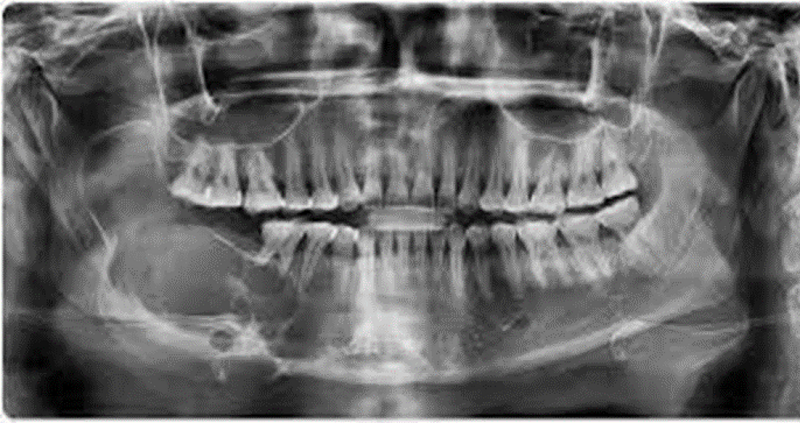

{"name":"Oral Path ID Chapter 6-9", "url":"https://www.quiz-maker.com/QPREVIEW","txt":"This condition is linked with Keratinosis of the palms of the hands & the soles of the feet. Individuals with this condition are likely to experience tooth mobility and premature tooth loss., This Term is used to describe The Appearance of type III (hypomaturation) Amelogenesis Imperfecta, Radiographs of a person with this condition appear to have a multilocular or “soap bubble” appearance","img":"https://www.quiz-maker.com/3012/CDN/92-4508546/final-pic-1.png?sz=1200"}